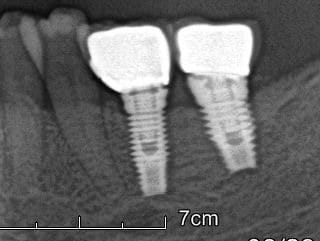

Voici la radio implants poses en 2007.

La radio ou tout va bien c'est 2009, et l'autre c'est aujourd'hui.

En bouche, asymptomatique, mais suppuration sulculaire presente. Pas de mobilite pour le moment.